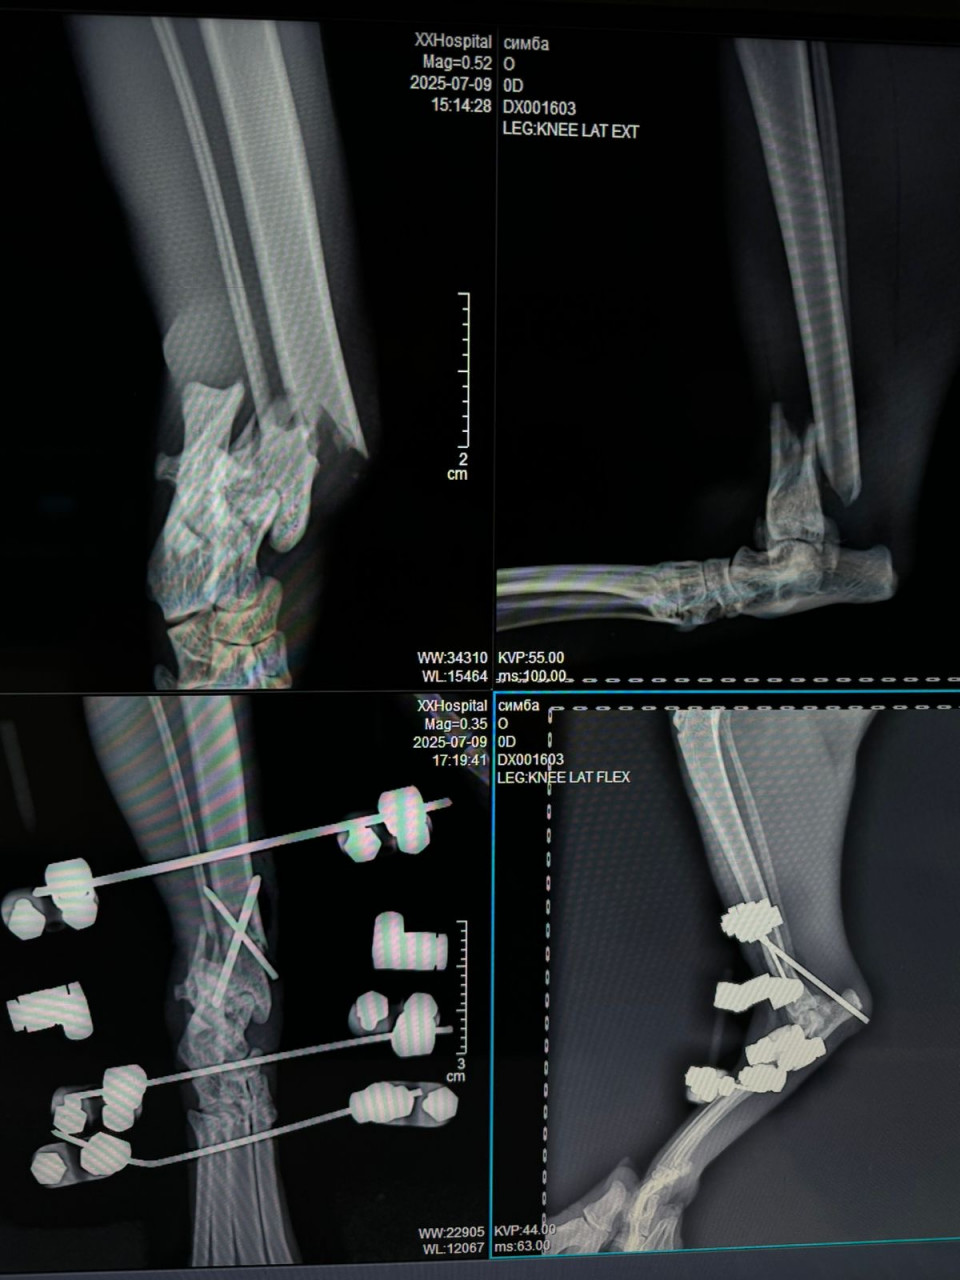

Добрый вечер, дайте свою оценку пожалуйста  у котика был сложный перелом ( упал с пятого этажа ) сделали операцию, поставили аппарат элизарово, по рекомендации врача кот всегда находится в клетке , на днях съездили на рентген где показал перелом  как могло это произойти ? операция стоила не маленьких денег , со своей стороны соблюдала все рекомендации и тут такое ( врач другой дал свою оценку и сказал , что возможно не правильно поставлен аппарат , на большой сустав одна спица а желательно две ( посмотрите пожалуйста снимки, так ли это ( как бороться с клиникой которая провела операцию ?!( на первом снимке после операции, на втором сделаны вчера .. так же фото лапы сегодня , нащупала два выступа и теперь думаю кость это или спицы вставлены там

Здравствуйте. По снимкам видно, что перелом был действительно сложный, с раздроблением костей. Аппарат Илизарова установлен, однако на одном из суставов действительно стоит только одна спица, тогда как обычно рекомендуется 2 для более устойчивой фиксации. Это могло сказаться на стабильности конструкции и привести к смещению. Выступы которые вы нащупали могут быть как края костных отломков, так и элементы спиц. Чтобы точно оценить  нужен очный осмотр и повторный рентген в динамике.

Здравствуйте. Учитывая характер травмы после падения с большой высоты, даже при правильно установленном аппарате возможны повторные смещения или осложнения из-за высокой нагрузки и хрупкости костных отломков. То, что одна спица стоит на суставе, не всегда является ошибкой и многое зависит от конкретной техники и состояния кости в момент операции. Выступающие образования могут быть как части спиц, так и костные края  это уточнится при осмотре и свежем рентгене. Сейчас главное  не пытаться самостоятельно трогать аппарат, а как можно скорее показать животное врачу, чтобы решить вопрос о дофиксации или корректировке конструкции.